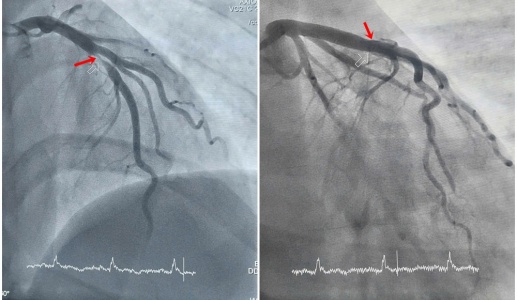

Thanh niên 29 tuổi phát hiện nhồi máu cơ tim cấp khi đi nội soi dạ dày

Một nam thanh niên đến bệnh viện làm nội soi dạ dày, tuy nhiên, trước khi thực hiện thủ...